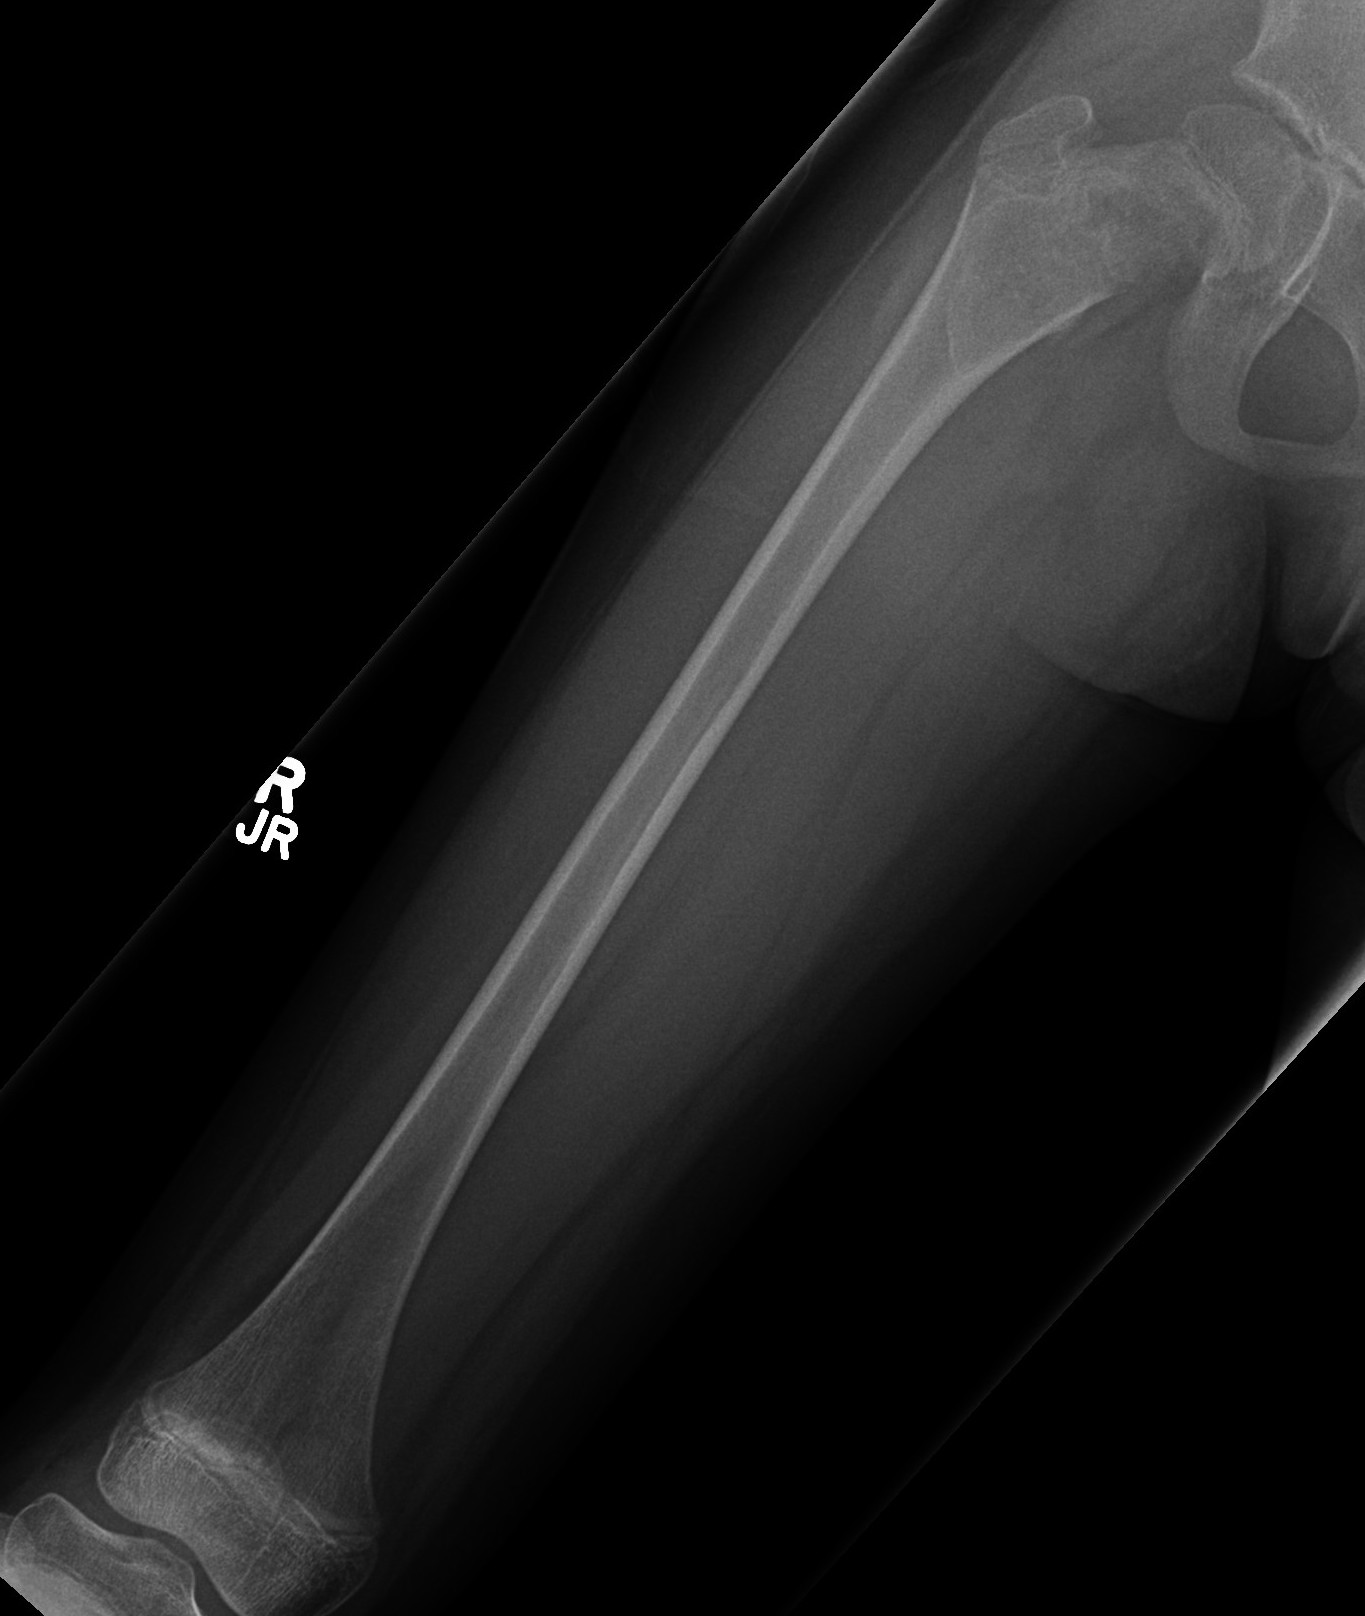

X-ray

Intramedullary lucent diaphyseal lesion with 'ground glass appearance'

- thinned, slightly bulged cortex

- ± endosteal scalloping

- may have angular deformity / bowing

Sabre tibia